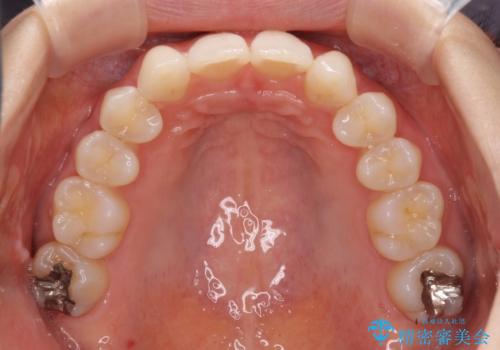

上顎前歯が2本欠損 インビザラインによる叢生の解消

- 深い咬み合わせと前歯のデコボコを気にして来院された患者様です。

上顎前歯2本が欠損しているため、妥協的なゴールを設定しインビザラインで矯正治療を行うこととしました。

上下前歯の大きさのアンバランスにより、深い咬み合わせと奥歯の咬みにくさがなかなか解決されず、治療に長期間を要することとなりました。